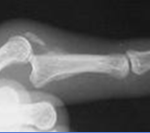

La radiographie standard de face et de profil du doigt et de la main est l’examen de base, à la recherche d’un éventuel fragment osseux. On appréciera sa taille et sa localisation.

La rupture s’accompagne d’un volumineux fragment de P3, véritable fracture articulaire avec sub-luxation dorsale de P3. La rétraction est quasiment nulle en raison du volume du fragment. |

| Type III : c’est une forme rare |